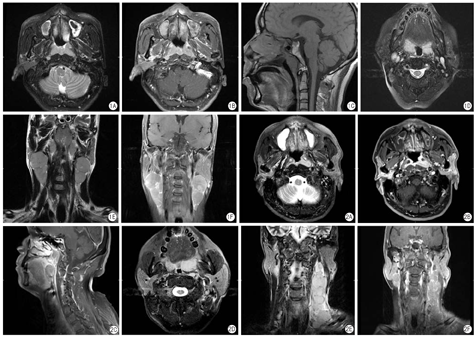

14例表现为鼻咽黏膜弥漫、对称性或大致对称增厚,列入弥漫浸润组(图1),占所有病例的60.1%;9例表现为局限性肿块,列入局限肿块组(图2),占所有病例的39.9%。

所有的病灶边缘均清楚、锐利,与周围肌肉、骨骼分界清楚,局部肌肉及颅底骨均未见异常信号,颅底筋膜亦未出现增厚,所有的翼腭窝均未见侵犯(图1A~C,图2A~C)。1例出现肿瘤直角嵌入邻近后方的头长肌现象,但与局部肌肉边界亦清楚,未出现浸润征象。

9例出现腭或(和)舌根扁桃腺浸润,其中7例来自弥漫浸润组,占腭或(和)舌根扁桃腺浸润病例的77.8% (7/9),均表现为腭或(和)舌根扁桃腺对称性肿大(图1D),占所有弥漫浸润组病例30.4% (7/23);2例来自局限肿块组,占腭或(和)舌根扁桃腺浸润病例的22.2% (2/9),表现为与鼻咽肿块同侧腭或(和)舌根扁桃腺肿大(图2D)。

13例患者出现颈部淋巴结浸润,其中11例为双侧基本对称淋巴结肿大(图1E、图1F),占颈部淋巴结浸润病例84.6% (11/13),均来自弥漫浸润组,占所有弥漫浸润组病例47.8% (11/23);2例颈部淋巴结不对称肿大(图2E、图2F),占颈部淋巴结浸润病例15.4% (2/13),均来自鼻咽局限肿块组,占所有局限肿组病例22.2% (2/9)。另有10例鼻咽淋巴瘤未出现淋巴结肿大,其中3例来自弥漫浸润组,7例来自局限肿块组。

在13例出现淋巴结浸润的病例中,12例最大径淋巴结位于II区,1例位于颌下间隙,来自局限肿块组。